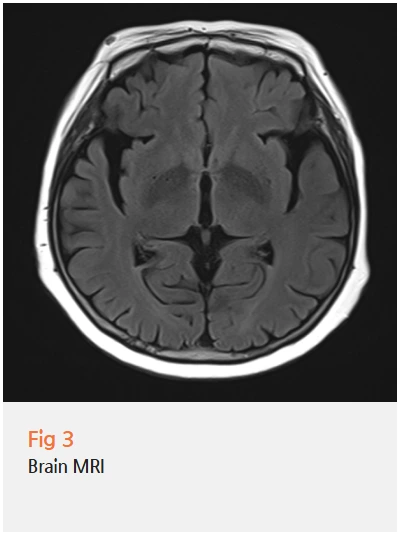

우선 허리 문제부터 확인하기 위해 당일 요추 MRI 검사를 시행했어요.

검사 결과 추간판 탈출증이 확인됐고,

이로 인한 신경 압박으로 다리 통증과 저림이 나타나고 있었습니다.

허리 치료를 위해 통증의학과 원장님과 협진해

CI(C-arm Intervention) 주사치료를 시행했고,

다행히 허리와 다리 통증은 많이 호전되셨어요.